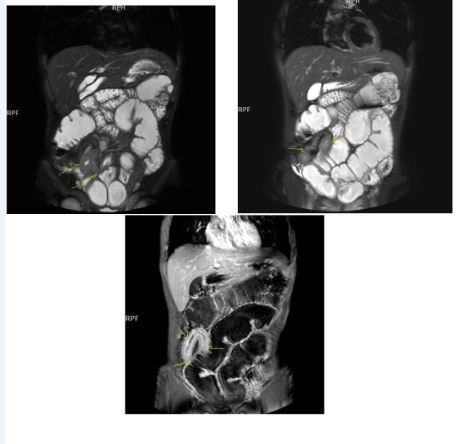

Chronic disease without active inflammation; Bowel wall thickening and enhancement on postgadolinium T1W images plus low signal intensity on T2W-FS images with possible stenosis and obstruction due to fibrosis, chronic disease with active inflammatoryexacerbations;these conditions can overlap with active inflammation, require longitudinal repeated scanning7, 12, 14, 20,26, 27, 28, 29, 30 (Figure 5a-b, Figure 6a-b)

Figure 5a.Enhancing bowel segments due to Crohn’s disease, on T1W post-contrast axial image, luminal enhancement is predominant, shown at 62 years old female with mild disease status.

Figure 5b.İrregular bowel wall and luminal enhancement of ileum, with loss of valvula conniventes on T1W coronal post-contrast sequence, seen on 26 years old male with moderate inflammatory bowel disease.

Figure 6a.Diffuse homogeneous contrast enhancement on the bowel wall and mucosa due to Crohn’s disease, seen at T1W post-contrast axial image, indicated at 23 years old male with mild disease status.

Figure 6b.Heterogeneous bowel wall and mucosa involvement with collaborating skip lesions, specific for Crohn’s disease, predominant in ileum and terminal ileum which are shown at T2W coronal sequence after OCA, regarded at 39 years old female with severe disease.